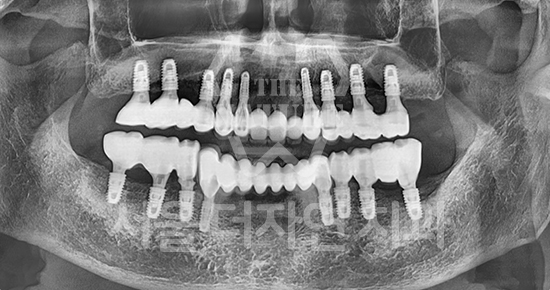

Full-mouth implants are highly advanced treatment

that require precise upper and lower occlusal harmony.

Patients themselves have proven us to be

a clinic specialized in full-mouth implant surgery.

Full-mouth implants are among the more complex dental procedures. They require careful decision-making, precise diagnosis based on each individual condition, and ongoing postoperative care after placement. With extensive experience in full-mouth implant treatment, Seoul The Nature Dental Clinic can provide systematic planning, placement, and follow-up care. Many patients continue to visit us through recommendations as a trusted clinic for full-mouth implants.

Dentures VS Full-Mouth Implants